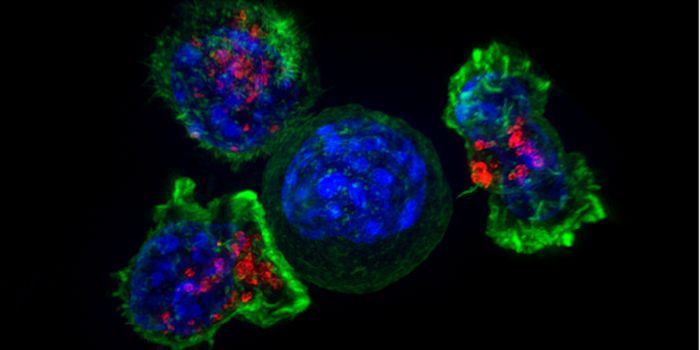

NOV 13, 2017ImmunologyThe battle between the immune system and growing tumors involves natural killer (NK) cells and a protective barrier put ...